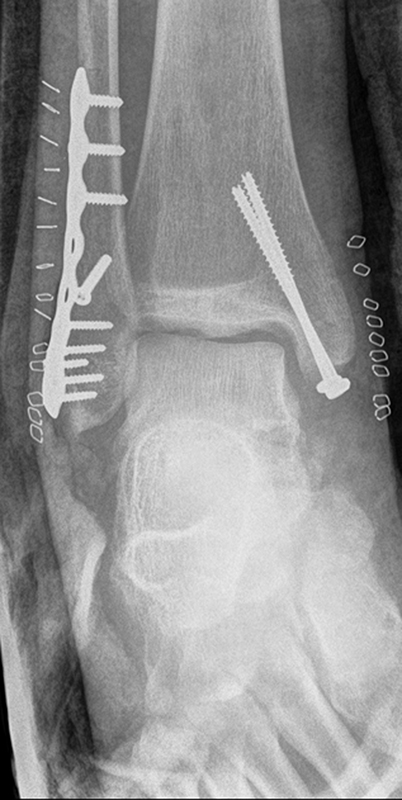

Die Versorgung von AO 44-B Frakturen erfolgt über einen längsverlaufenden lateralen Zugang. In der Regel gelingt eine suffiziente Stabilisierung mittels interfragmentärer Zugschraube (bei langem Frakturverlauf ggf. 2 Zugschrauben) und einer zusätzlichen Neutralisationsplatte (Abbildung 9 & 10).

Bei multifragmentären Frakturen (AO 44-B2.3) oder bei schlechter Knochenqualität sollte die Versorgung mittels winkelstabiler Plattenosteosynthese erwogen werden (Abbildung 11 & 12).

Frakturen vom Typ AO 44-C werden in der Regel mittels interfragmentärer Zugschraube und Neutralisations-Plattenosteosynthese versorgt. Die Versorgung von Frakturen mit metaphysärer Trümmerzone (AO 44-C2) ist mitunter anspruchsvoll. Entscheidend ist die Wiederherstellung der korrekten Länge und Rotation der Fibula. Die Verwendung von winkelstabilen Implantaten bietet hier eine höhere Stabilität. Bei Typ C Verletzungen liegt definitionsgemäß eine Syndesmoseninsuffizienz vor, die entsprechend versorgt wird (siehe Abschnitt Syndesmoseninsuffizienz). Bei hohen Fibulafrakturen (AO 44-C3, Maisonneuve-Frakturen) steht die Versorgung der Syndesmoseninstabilität im Vordergrund. Eine zusätzliche Versorgung der proximalen Fibulafraktur ist nicht erforderlich.